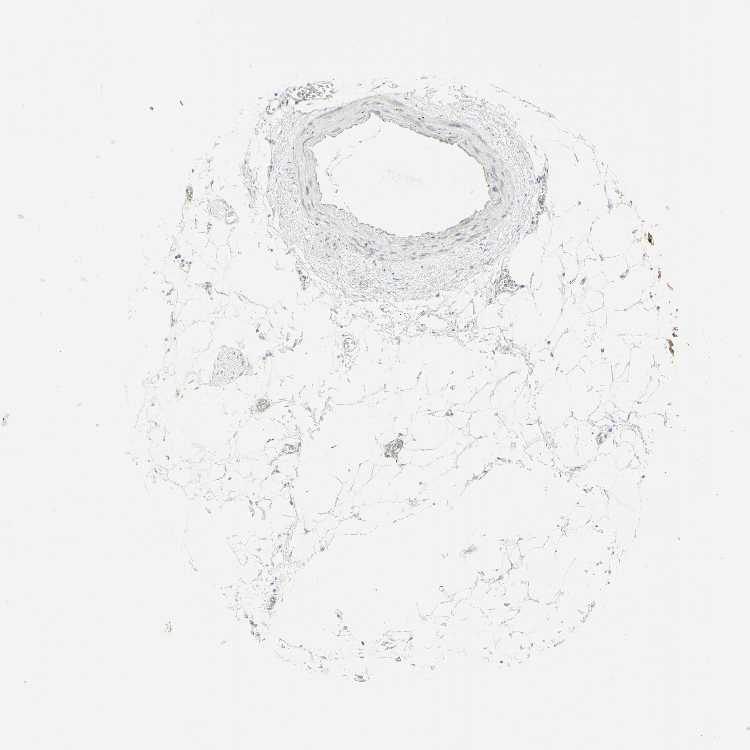

SOFT TISSUE 1 - Antibody stainingi

Antibody staining in the annotated cell types in the current human tissue is reported as not detected, low, medium, or high, based on conventional immunohistochemistry profiling in selected tissues. This score is based on the combination of the staining intensity and fraction of stained cells.

Each image is clickable and will lead to virtual microscopy that enables deeper exploration of all samples and also displays staining intensity scores, fraction scores and subcellular localization as well as patient and tissue information for each sample.

Antibody HPA011036Antibody HPA011057

Chondrocytes Not detectedNot detected

Fibroblasts Not detectedNot detected

Peripheral nerve Not detectedNot detected